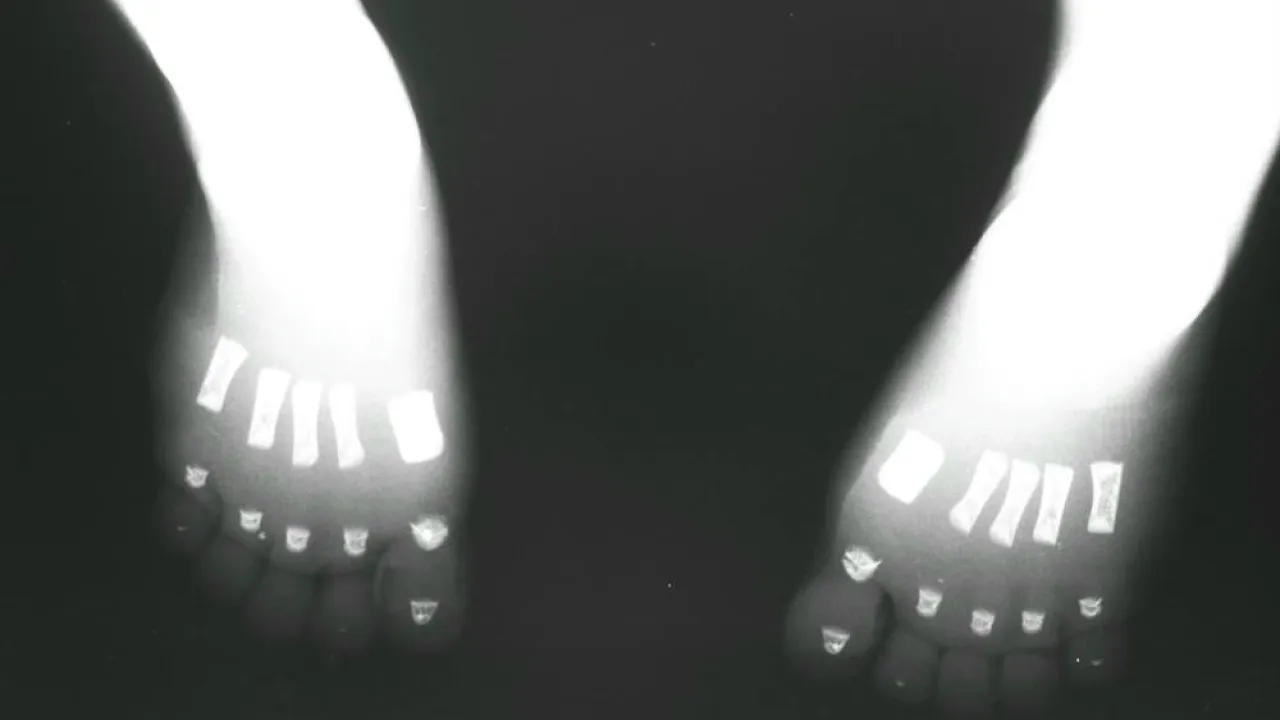

Foot, Twin reversed arterial profusion sequence

Skeleton and body morphology, Twin reversed arterial profusion sequence

Skeleton, Twin reversed arterial profusion sequence